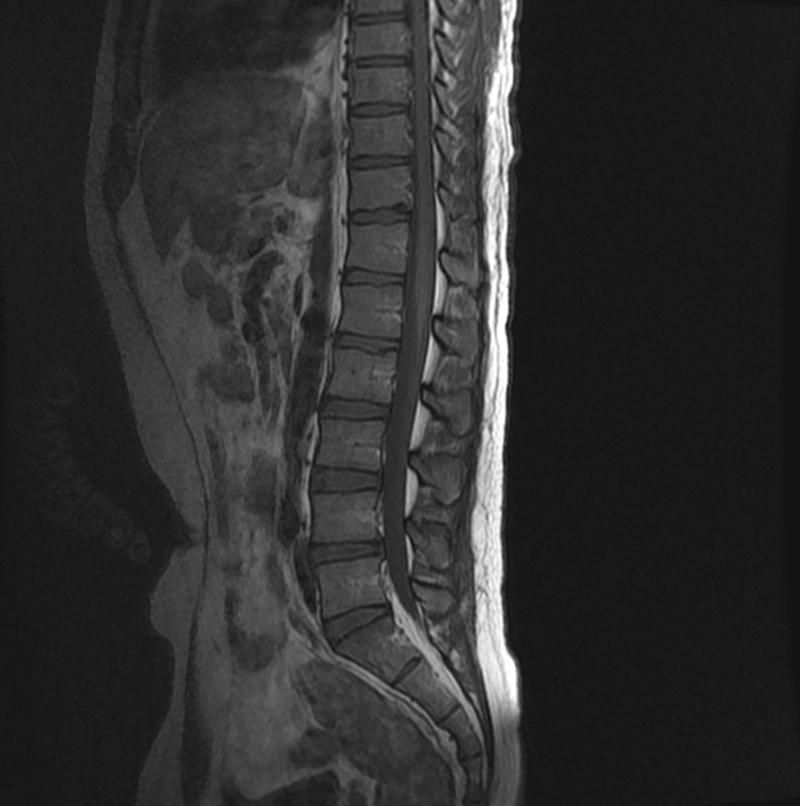

척수 mri 탈수초 현상 질문(사진 유)

혹시 해당 척수 mri에 탈수초 현상이 포착이 되는지요?

흉추 쪽에 넓고 길게 비교적 옅은 색이 보여서 여쭈어 봅니다ㅠ

• 1번 째 사진